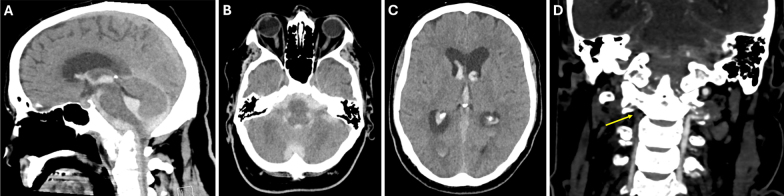

Observations: A 65-year-old male presented with worsening chronic cervicalgia, occipital headaches, and unstable tandem gait. CT revealed basilar impression with severe atlantoaxial erosion and instability, absent on imaging 8 months prior. MRI showed high-grade CCJ stenosis without myelopathy, due to CPPD. Before treatment could be initiated, the patient was suddenly found unresponsive. CT showed posterior fossa hemorrhage due to VA dissection, with secondary obstructive hydrocephalus. An external ventricular drain was placed, followed by coil VA embolization. After halo vest placement, CCJ alignment was restored and the patient underwent occipitocervical fusion. Following prolonged rehabilitation, he regained independent living without significant neurological sequelae.

Lessons: This is the first reported case of VA dissection with posterior fossa hemorrhage secondary to basilar impression due to CPPD. Inflammatory arthritides of the CCJ may cause rapidly progressive atlantoaxial erosion, predisposing one to unstable basilar impression and VA dissection. Awareness of this risk is crucial in the surgical management of inflammatory basilar impression, where preoperative vascular imaging may be warranted in selected cases. https://thejns.org/doi/10.3171/CASE25332.